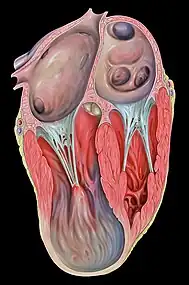

Ventricular aneurysm

| Aneurysm of heart | |

| Heart left ventricular aneurysm short axis view | |

Ventricular aneurysms are one of the many complications that may occur after a heart attack. The word aneurysm refers to a bulge or 'pocketing' of the wall or lining of a vessel commonly occurring in the blood vessels at the base of the septum, or within the aorta. In the heart, they usually arise from a patch of weakened tissue in a ventricular wall, which swells into a bubble filled with blood.[1] This, in turn, may block the passageways leading out of the heart, leading to severely constricted blood flow to the body. Ventricular aneurysms can be fatal. They are usually non-rupturing because they are lined by scar tissue.